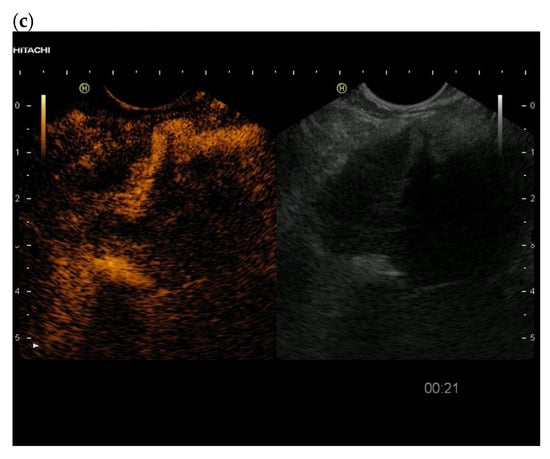

3.4. CEUS and CH-EUS

| Colour Doppler Imaging | RCC metastases are hypervascularized Most other pancreatic metastases are hypovascularized | No hypervascularization | Hypervascularized |

| Cases | CEUS | CH-EUS | ||

|---|---|---|---|---|

| Arterial Phase | Venous Phase | Arterial Phase | Venous Phase | |

| RCC metastases [83] (n = 4) | Hyperenhancement, Early | Hyperenhancement | ||

| RCC metastases [61] (n = 3) | Hyperenhancement, homogeneous pattern | Slow washout | ||

| RCC metastasis [86] (n = 1) | Hyperenhancement, Inhomogeneous pattern | No washout | ||

| Melanoma metastasis [63] (n = 1) | Iso- to slightly hypoenhanced | Hypoenhanced | ||

| Melanoma metastasis [87] (n = 1) | Isoenhanced | Hypoenhancement of the peripheral rim, central non-enhancement | ||

| Melanoma metastasis [61] (n = 1) | Isoenhanced, heterogeneous | Fast washout | ||

| SCLC metastasis [83] (n = 1) | Hyperenhancement | Rapid washout | ||

| Breast, ovarian, colon metastases, sarcoma metastases [61] (n = 6) | Hypoenhancement, homogeneous or heterogeneous | Fast or slow washout | ||

| Lymphoma metastasis [61] (n = 1) | Hyperenhancement, homogeneous pattern | Fast washout |